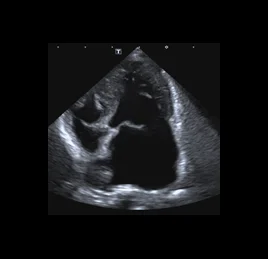

• 퇴행성 판막질환

• 동맥관 개존증 - PDA

• 폐동맥고혈압